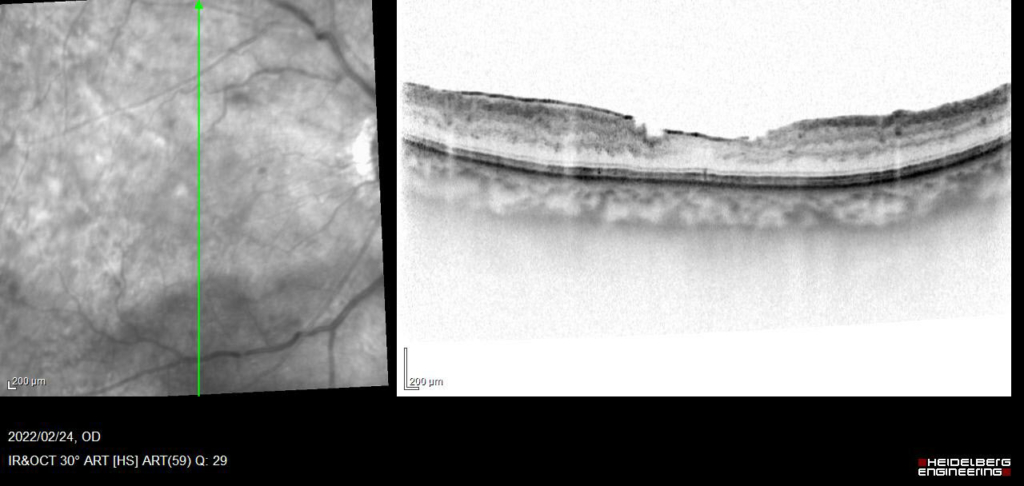

主訴 右眼 徐々にかすむ

既往歴 30年前からの糖尿病(HbA1c:7.4)

約4か月 抗VGEF(ラニビズマブ)の硝子体注射4回施行後、黄斑浮腫は注射直後に一時的に改善するが、4wで黄斑浮腫は著明に再発する。

発症後約10か月、抗VGEFの硝子体注射後5Wで黄斑浮腫のみられない状態が維持できるようになった。